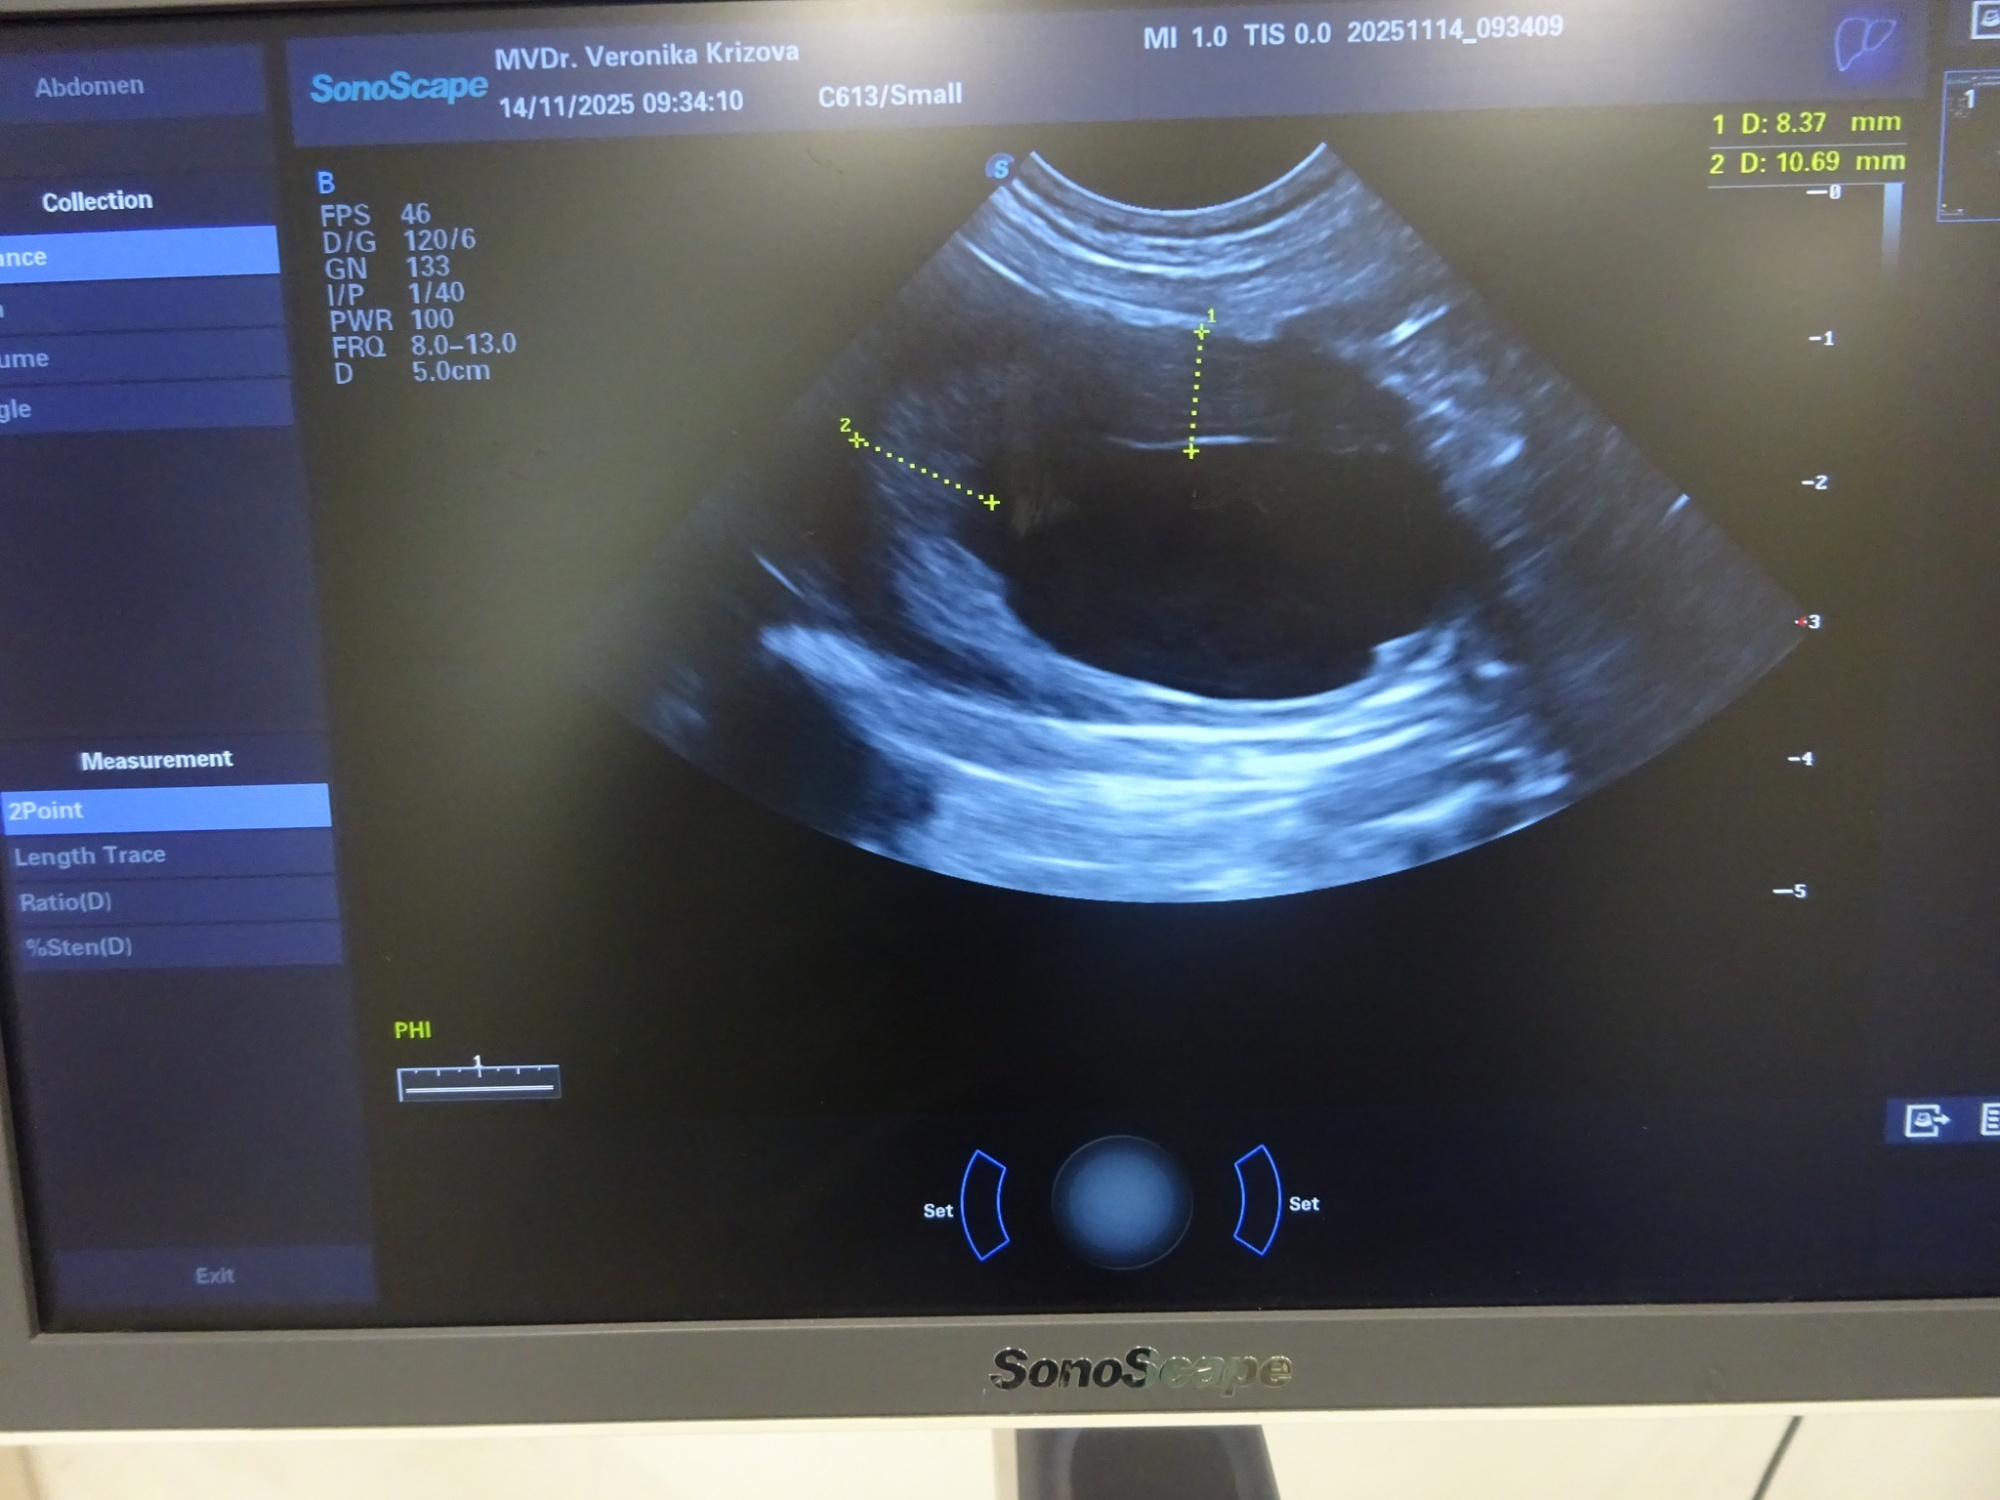

Dnes byl náš Pan ředitel Knoflíček na dalším kontrolním Sonu v ordinaci naší paní doktorky Veroniky, vyšetřovala ho paní doktorka Magda Hrůzková.

A závěr? Agresivní nádor v močovém měchýři se už téměř 2 měsíce nezvětšil, co víc si přát? Ale pořád ten nádor vypadá hrozivě. Krev je OK.

Knoflíček i trošku přibral, baští jak o závod a několikrát denně lítá na zahradě jako drak. Sice před 10 dny zase krvácel, ale po zvýšení dávky homeopatik během dne krvácení ustalo.

A tak stále věřím, že jeho pověstný úsměv a radost ze života nás budou provázet ještě hodně dlouho.. :-)